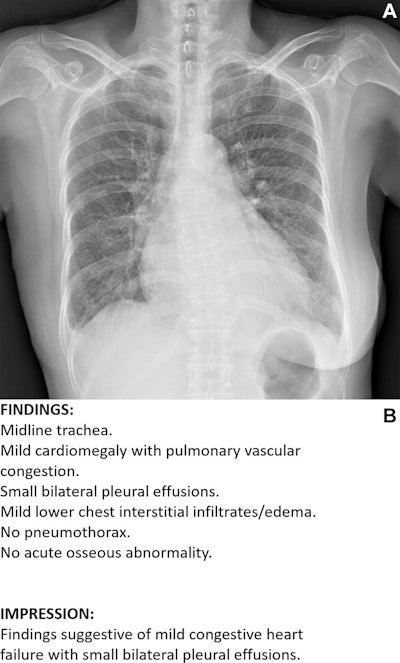

Example of an acceptable AI–generated chest x-ray report. (A) Anteroposterior chest x-ray in a 68-year-old female patient who visited the emergency department because of acute-onset dyspnea shows an enlarged heart, bilateral pleural effusion, and bilateral interstitial thickening, suggesting heart failure and interstitial pulmonary edema. (B) The AI-generated report appropriately describes the findings of the x-ray and suggests a possible diagnosis. All seven thoracic radiologists evaluated the AI-generated report as acceptable without revision.RSNA